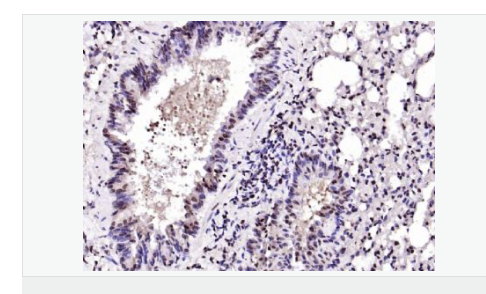

| 研究領域 | 腫瘤 細胞生物 神經生物學 細胞周期蛋白 |

| 產品應用 | ELISA=1:5000-10000 IHC-P=1:100-500 IHC-F=1:100-500 IF=1:100-500 (石蠟切片需做抗原修復) not yet tested in other applications. optimal dilutions/concentrations should be determined by the end user. |